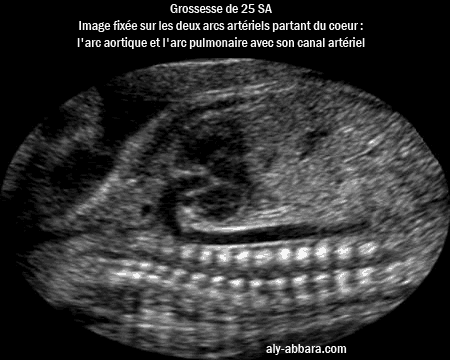

Image échographique

montrant le cœur fœtal à 25 SA :

les deux arcs artériels partant du cœur, c'est-à-dire l'arc aortique avec sa crosse et l'arc

pulmonaire avec son canal artériel communicant avec l'aorte

Coeur foetal à 25 SA : image montrant les deux arcs artériels partant du coeur, l'arc aortique avec la crosse de l'aorte et l'arc pulmonaire avec son canal artériel communicat à l'aorte